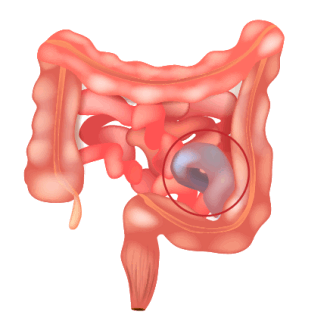

2. Механическая непроходимость: а) странгуляционная (заворот, узлообразование, ущемление; б) обтурационная (интраинтестинальная форма, экстраинтестинальная форма); в) смешанная (инвагинация, спаечная непроходимость).

- Механическая (странгуляционная и обтурационная). Бывает различных форм, появляется из-за возникновения препятствия на пути движения пищевой массы, например, камней, инородных тел, опухолей и кист других органов, сдавливающих просвет кишечника. Тяжелым состоянием считается заворот или узел из петель кишечника.